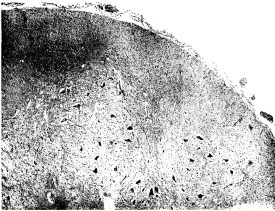

| 3. | Lumbar cord in case of scurvy | 105 |

| 4. | Lumbar cord in case of scurvy. Focal degeneration | 105 |

| 5. | Bone in scurvy. Microscopic pathology | 108 |